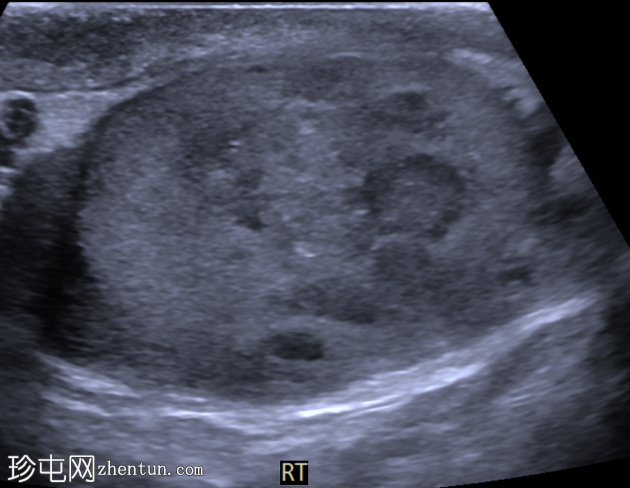

睾丸混合性生殖细胞瘤

右侧睾丸肿块,伴间歇性疼痛4个月。

横切面

右侧睾丸内可见一大小约3.0 x 5.0 cm的异质性分叶状低回声肿块。肿块内未见囊性区域或钙化。彩色多普勒超声检查显示肿块内血流丰富。左侧睾丸正常。